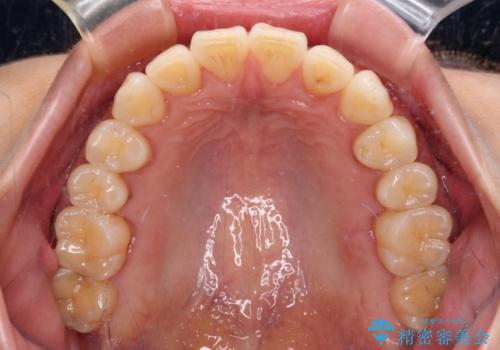

- 奥歯の咬み合わせと、上下前歯の隙間を気にして来院された患者様です。

上顎の歯列全体が、下顎歯列に対して前方に位置しており、その影響で上顎前歯がやや前方に突出している状態でした。

横顔の印象から、抜歯をして積極的に口元を引っ込める必要はなかったため、アンカースクリューを用いて上顎歯列全体を後方に移動させることとしました。